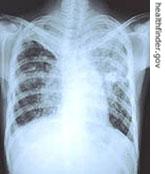

Doctors also use an X-ray examination to show if there is evidence of TB infection, such as damage to the lungs. Another way to test for the presence of active tuberculosis is to examine the fluids from a person’s mouth.